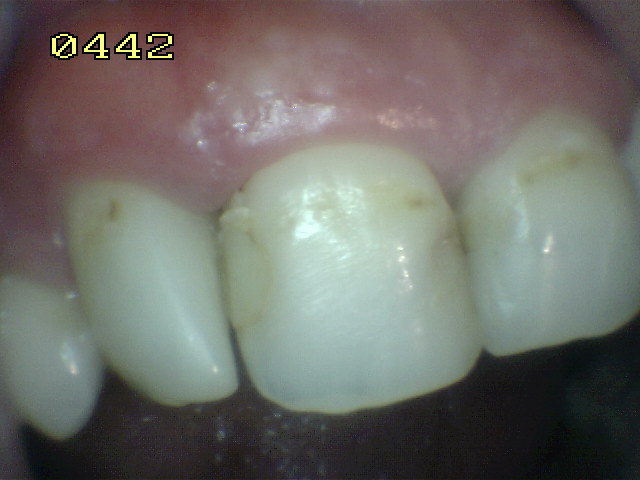

Tratamiento de hipoplasia del esmalte

en 21, semicarilla lumino-activada |

| Caso a tratar |